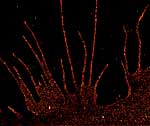

Insulin wird seit vielen Jahrzehnten gegen Diabetes eingesetzt. Doch erstaunlicherweise ist nur wenig darüber bekannt, wie es sich in den Zellen des Menschen verhält. Das erforschen nun Wissenschaftler vom Biozentrum in Kooperation mit einer dänischen Firma.Kopenhagen, im September 2014: Professor Markus Sauer vom Biozentrum der Universität Würzburg hält auf einem Symposium an der Universität Kopenhagen einen Vortrag. Er stellt die hochauflösende Mikroskopietechnik dSTORM vor, die er selbst entwickelt hat: Sie liefert extrem scharfe Bilder von einzelnen Biomolekülen, etwa von den Zuckern und Proteinen auf Körperzellen.

Bildunterschrift: Mikroskopietechnik dSTORM: Verteilung des beta-1-adrenergen Rezeptors auf der Membran einer Nierenzelle mit fast molekularer Auflösung. Die fädigen Strukturen sind Ausläufer der Zelle.

Bildquelle: Julius-Maximilians-Universität Würzburg